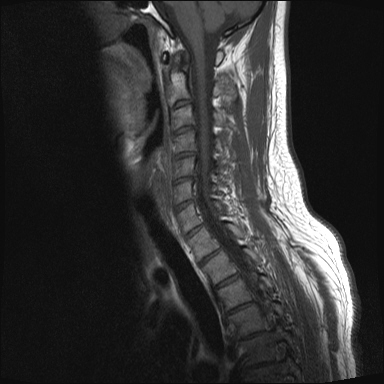

ȸ ϸ鼭 ۼ Դϴ. Ű 172 72 35 ˰Ե ͳ õ ijħ ǥغ ϱ ȣϽ 1C.ڵӸ 1C.ٸǷ 1C.ټ Ǹ 1C.ٱ () 1C.߷ () 1C.Ƿ () 2C.ھȱ, 2C.ڴ 2C.ھ˷⼺(˷) ḷ 2C.ٴ, 2C.ٰḷ 2C., 2C.ٺ, 2C.ٸ 2C.پ˷⼺(˷) 3C.ġ Ű 3C. 4C. 6C.ڸ 6C.ھ Ḳ 6C.ڻ 1T.ȣ 4T. 3T.ȯ, 5T.ȯ ҷ, 6T.ټ 6T.ٽƮ 9T.˷ 10T.ٸǷ 2L. 㰡 2L.ȣ 3L. 3L.ڹ 4L.° 4L.ھƷ 4L.ڿ, 4L.ڵ Ʒ 5L.ڴٸ Ʒκ̳ 5L.ڹ߸̳ õ().¦ٸ ()ũ( ߰Ż) Ը Ͽ ũ(߰Ż), ũ(߰Ż)ġ, , Ḳ , , Ḳ ġ ȱ ǰϰų ڸ, , ڰ , , Ǵ ġ ô ¦ٸ(ٸ̰ ٸ) , 㸮 ̳ ġ Ƹ ġ ħ ߷, , нɷ 帶, ɱٰ, ɺ ڸǥغ ǥغ ϰ ߴ ġ 1. ũ 1) ߺñ: 1 Ӹ ־ ʹ 2)˻ : ** x-ray MRI Ȯ 3,4,5 ũ ̸, Ư 4 ũ ¦ Ƣ . 3)ġ: Ű漺 , ġḦ ʾҰ, Ư ǿ ħ °, Ȱġ(Ȳ,ħ, ȸ ) . 4)ġ : 1.Ͻ ȿ ־, ð 2. 㸮() 1) ߺñ: 3 ϱ ٳѱ⸦ ڱ 㸮 , ģ ƮĪ شٸ 㸮 ȭ ƮĪ Ʋ . 2)˻ : ǿ 㸮 ġ . 3)ġ: ħ ȰġḦ 4)ġ :Ͻ ȿ ־ ɰų 㸮 3. ڰ 1) ߺñ: ڰ̰ ִ Ȯ 5 Ǵܵ 2)˻ : 6~7ð 2~3ð ڸ , ȣ 3)ġ: ġḦ ް , ڰ *** ߿ Ƽ ϰ 4)ġ : ڸ 4. 1) ߺñ: 2~3 ְų Ͻ ־ 2)˻ : ˻縦 ʾ, ʰ ô ó 3)ġ: 4)ġ : 5. ô 1) ߺñ: 3 ڿ ɾƼ ٸ µ ٸ ª 2)˻ : 7 Ȱ X-RAY ణ ô ִٰ Ǹ 3)ġ: ġ 4)ġ : Ͻ 6. (˷ ḷ) ȱ 1) ߺ: 5 2)˻ : Ű 3)ġ:1~2 ѹ ް Ⱦ ֱ ְ 4)ġ : , ħħϰų 7. , Ѽ ȣ ߺñ: ɸ Բ ڰⰡ , ڸ, ä, 2)˻ : Ḧ ʾ, ڰ Ⱑ ư, Ѽ Ҵ Ȳ µ ϰ ȸ ȭ ˷ֽ ǥغ ϴ ڸ ϴ. 㿡 ħ ȸԲ ˷ֽ Ư ġü ġὺƮĪ Բ ġ ȭ ʰ ȸǴ ڼ ϴ ϴ. ˷ֽ ͵ ̳ ǰ ͳݿ ִ ٸ Դϴ. ϴ ȭ Ÿϴ. ϴ. پٰ ϴ. ϴ پų ϴ. 30и 30 ̻ ϶ ϼ̽ϴ. 30иٴ ϰ ҷ ߽ϴ. Ȳ ٷ ϴٰ ٽ ϴ. ķ 鵵 Ÿϴ. γ ȸԲ ڵȽϴ. ٽ ȭּż Ȳ ϰ ʰ ּ̰ ڼ ణ ߸ϰ ־ ֽð ʰ ˷ּ̽ϴ. ȭ Ŀ ߰ ȭ ߾ ߴµ ϴٰ 1 ȭ ѹ ʾҾϴ. ˷ֽ ˷ֽ 뿡 ణ ̴ ε ̼ϰ ٸ ̷ Դϴ. ʰ ϴ ڼ ü ٽ ϰ ˷ּ̰ а ߴص ϰ ˷ֽ θ ϶ ϼ̽ϴ. ˷ֽŵ Ȱ ϰ غ ı øڽϴ. ȸ 㵵 ű Դϴ. ۼ ıԴϴ. http://najari.kr/Board/index.php?Code=free1&No=5141&action=View&st=&sn=&sc=&Keyword=&Page=1 |